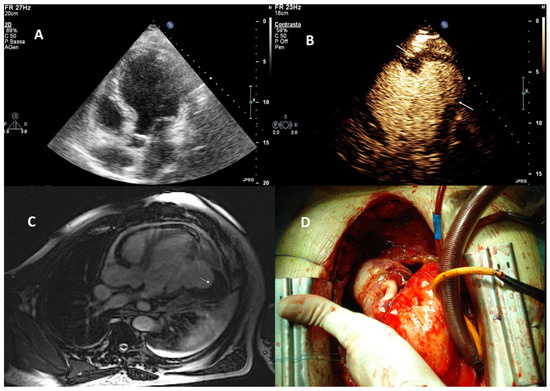

| Imaging method | Low-MI-contrast-specific imaging, additional intermediate-MI imaging in case of apical aneurysm for assessment of thrombus in the aneurysm |

| Imaging planes | Standard apical views and apical sweeps to assess the aneurysm for thrombi |

| Contrast application | Bolus injections |

| Typical finding | 1. Hourglass/ace-of-spades shape of apical LV cavity 2. Apical myocardium appears dark in late systole due to compression of the intramyocardial vessels 3. Apical aneurysms +/− thrombi in some patients |

| Alternative imaging | MRI useful for scar/fibrosis imaging and display of apical aneurysms CT in patients with contraindication for MRI and UEAs |